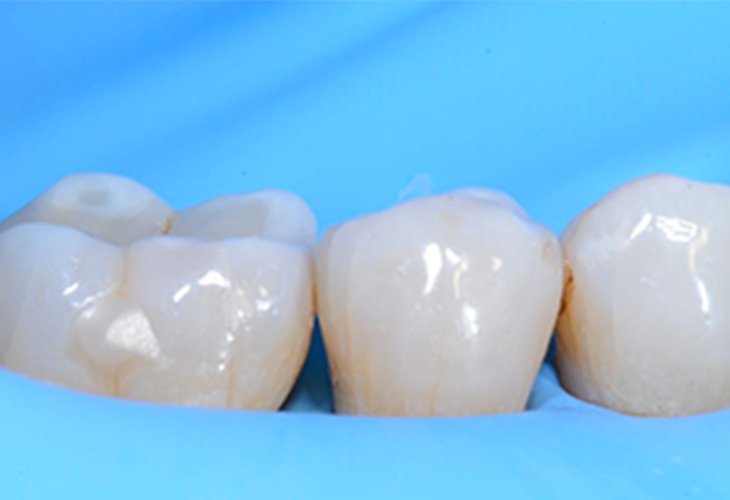

12. Vue post-opératoire de la restauration